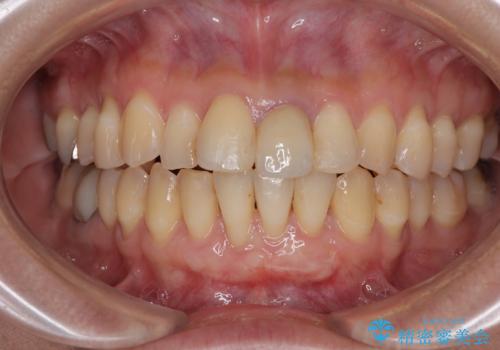

- 他院で矯正治療を終えた結果、下顎前歯の歯肉が退縮してしまい、歯根が見えていることが気になるとのことで来院された患者様です。

歯肉退縮に対して、上顎からの結合組織移植術(CTG)により、歯根の被覆を行うとともに、歯肉の厚みを増すことで将来の退縮リスクを抑制することとしました。

一度の処置で大幅に露出部の被覆に成功しましたが、更なる厚みと被覆を希望されて2回目の処置を行いました。

歯根部周辺の歯肉が非常に分厚くなり、今後の退縮リスクが大きく軽減されました。